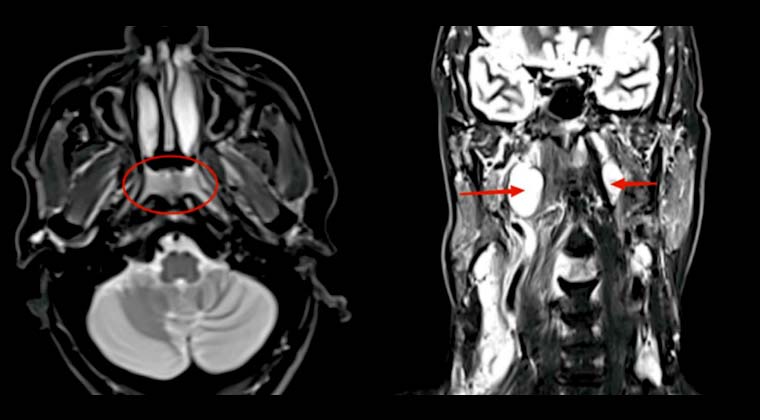

Злокачественное новообразование носоглотки (неороговевающий недифференцированный рак носоглотки)

Симптомы: дискомфорт в области шеи, преимущественно боль

Назначенная доза: PGTVnx 70,29 Гр/2,13 Гр/33 фракций, PGTVnd 67,98 Гр/2,06 Гр/33 фракций, PTV1 62,04 Гр/1,88 Гр/33 фракций, PTV2 54,12 Гр/1,64 Гр/33 фракций

Через восемь месяцев после лечения контрольная МРТ показала уменьшение опухоли носоглотки и лимфатических узлов с положительным диагнозом, регресс утолщения слизистой носоглотки.

До лечения:

После лечения: